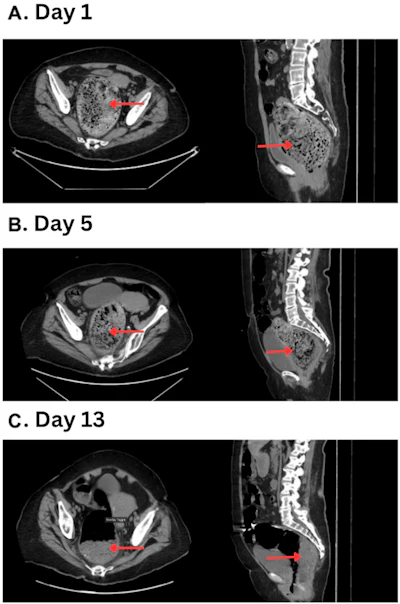

The team reported results from a case that involved an 82-year-old woman with dementia, type 2 diabetes, hypertension, hypothyroidism, chronic gastritis, and depression who presented with acute abdominal pain. She had not produced stool or passed gas via the rectum for several days prior to admission. A physical examination revealed middle and lower abdominal tenderness and distension; CT imaging of the abdomen and pelvis showed a fecaloma 12.2 cm × 10.5 cm in the woman's sigmoid colon and rectum. There was no evidence of perforation. Five days of conservative treatment (polyethylene glycol, senna, mineral oil, and sodium phosphate enemas) failed to dissolve the fecaloma or resolve the patient’s symptoms: a follow-up CT exam showed no change in the size of the fecaloma.

On hospital day 13, the woman received an enema of 1,000 mL of Classic Coca-Cola. The day after this treatment, another CT exam showed a 50% reduction in fecaloma size. The patient underwent another 1,000 mL Classic Coca-Cola enema on hospital day 16, which resulted in complete resolution of her symptoms as indicated on CT imaging. She was discharged on a maintenance bowel regimen.

Panel A demonstrates the significant fecal impaction on admission. Panel B indicates fecaloma persistence after conservative measures on hospital day 5. Panel C shows significant reduction in size of the fecaloma one day after administration of a classic Coca-Cola enema. The red arrows indicate stool burden over the hospital course.Cureus